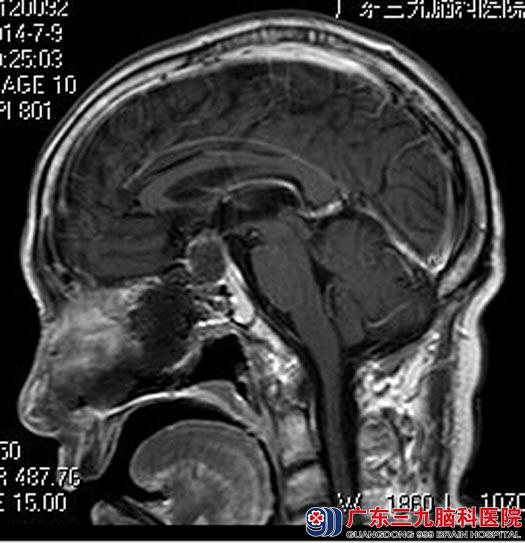

上级医院就诊,医生建议行头颅CT检查,提示鞍区占位。广东三九脑科医院进一步头颅MRI检查提示:鞍区示一囊实性占位性病变,大小约为2.1cm×2.1cm×1.8cm,考虑垂体大腺瘤可能。